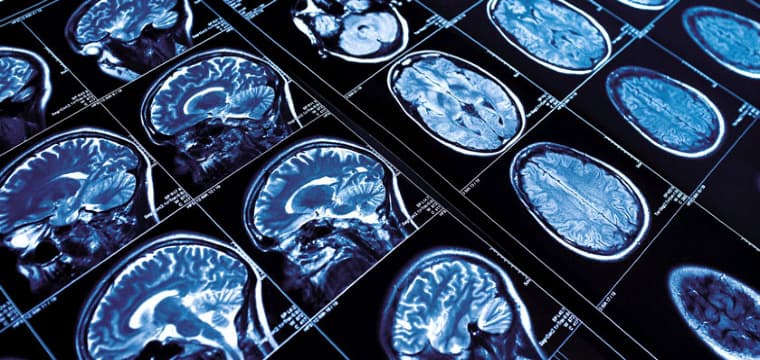

Advanced imaging techniques play a crucial role in diagnosing cerebrovascular disease. One of the most commonly used imaging methods is computed tomography (CT) scanning, which provides detailed cross-sectional images of the brain, helping to identify areas of bleeding, infarction (tissue death due to lack of blood flow), or other abnormalities. Magnetic resonance imaging (MRI) is another powerful tool that offers high-resolution images of brain structures and can detect early signs of cerebrovascular disease, such as small strokes or transient ischemic attacks (TIAs).

In addition to these imaging techniques, vascular imaging methods are often employed to visualize the blood vessels in and around the brain. Carotid ultrasound, for example, uses sound waves to create images of the carotid arteries in the neck, allowing healthcare providers to assess for narrowing or blockages. Magnetic resonance angiography (MRA) and computed tomography angiography (CTA) provide detailed images of the brain's blood vessels, helping to identify aneurysms, arteriovenous malformations (AVMs), or other vascular abnormalities.